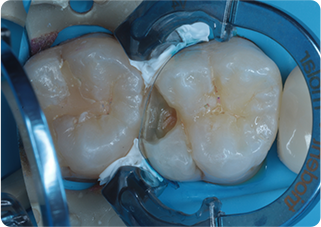

セラミックアンレー症例①

術前

むし歯除去

ラバーダム防湿

術後

| 主訴 | むし歯の治療をしたい |

|---|---|

| 治療期間/回数 | 2週間、2回 |

| 価格(税込) | 77,000円(税込) |

| リスク・副作用 | セラミックの破損、一時的な知覚過敏が生じる場合がある |

| ポイント | ラバーダム防湿をし、唾液や呼気の侵入を防ぎ湿度を下げることで、セラミックの接着力の向上を計った。接着力の向上により、脱離や破折の予防になる。 |